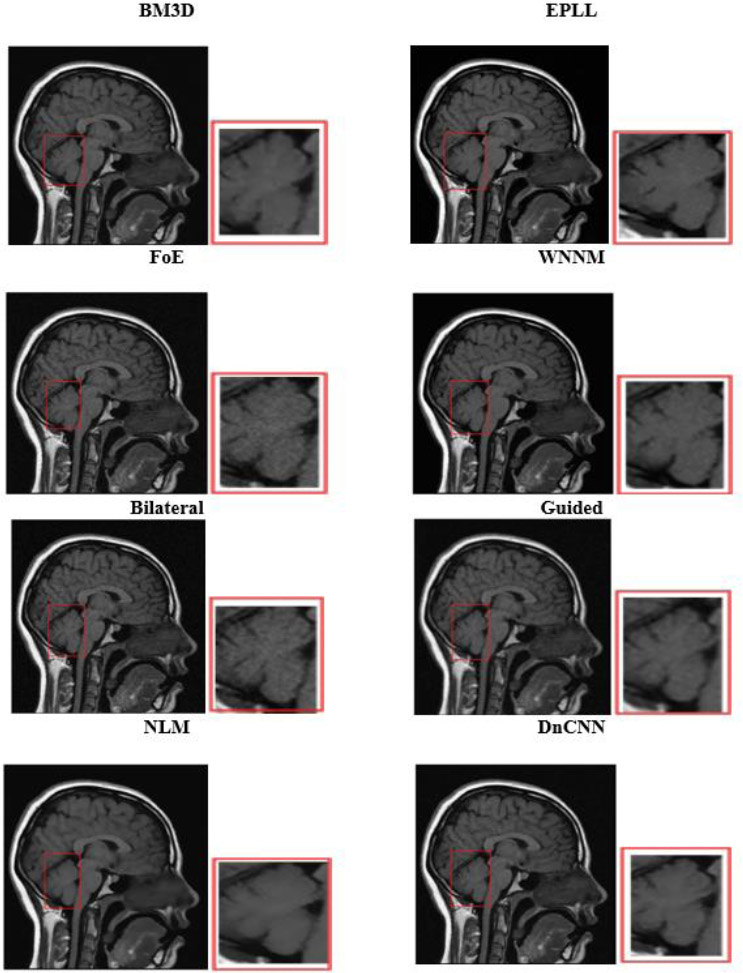

Visual analysis of the usual MRI and HRCT images is used to examine the qualitative performance of each denoising algorithm. Special attention was paid to anatomically relevant sites, such as fine pulmonary textures in HRCT and gray-white matter boundaries in T1-weighted brain MRI.

Run-time evaluation of different denoising algorithms.

The visual quality of the denoised images was determined on cropped and zoomed regions of interest (ROIs). The capability of the algorithms to minimize noise while preserving the most essential features, such as tumor borders, ventricular boundaries, or alveolar boundaries, was tested. Such an analysis is crucial, especially in medical imaging, where even slight degradation or excessive smoothing may obscure diagnostic clues. Perceived quality and artifact suppression are illuminated by visual comparisons, and quantitative measurements are corroborated.